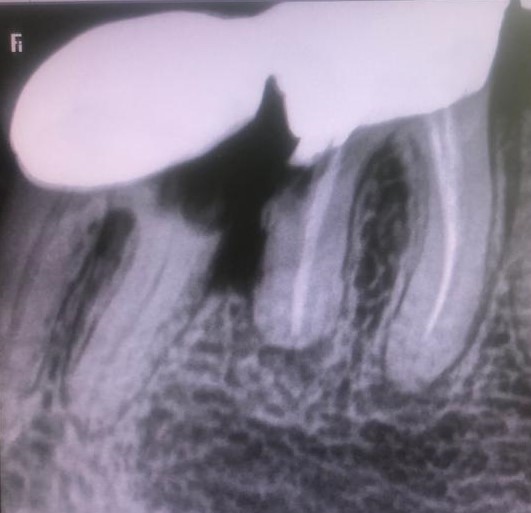

Presentamos un nuevo caso en el que la paciente presenta un gran dolor en su prótesis antigua (15 años) sobre dientes naturales tallados en zona inferior de molares. Es una paciente muy bruxómana, se unieron dos molares tallados con dos coronas. En el caso que presentamos el molar anterior estaba endodonciado ya antes de colocar la prótesis fija, pero el molar distal no. Y éste era la causa del gran dolor. Esto es por haberse filtrado creando caries y destrucción dentaria que llegaba al nervio. En conclusión, produciendo una gran pulpitis.

Esto provocaba en la paciente un gran dolor, pero ella no contemplaba en ese momento la opción de levantar la prótesis para explorar las piezas que había debajo, poder visualizar la destrucción dental y rehacer todo con una prótesis nueva. Por tanto, para quitar el dolor normalmente habría que haber hecho las extracciones de los dos molares, lo cual sería muy invalidante. En la clínica decidimos hacer una endodoncia de la raíz distal del último molar a través de la prótesis por la zona oclusal, y hacer odontosecciones de las raíces lesionadas sin quitar la prótesis. Ésta va permanecer tal como estaba.

Lo cierto es que las raíces  ya estaban bastante separadas de el resto de los molares correspondientes por su destrucción, lo que nos permitió la extracción de estas raíces en concreto. Teniendo en cuenta también que las raíces mesial y distal de cada molar no estaban unidas entre sí, sino que había una separación entre ellas.

La técnica quirúrgica para este menester es parecida a una apicectomía, pero en lugar de quitar solo el ápice radicular quitamos toda la raíz dental. Así pues lo que se hizo fue extracción de la raíz distal del primer molar y extracción de la raíz mesial del segundo molar. Con lo que la prótesis sigue teniendo dos pilares.

Con la secuencia de imágenes se comprende muy bien la técnica quirúrgica realizada.